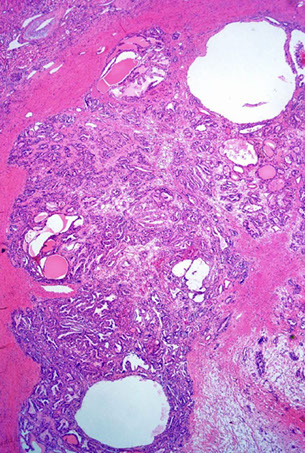

Xanthogranulomatous pyelonephritis

Staghorn calculus, E. coli, Proteus

- the result of suppurative sequela of chronic pyelonephritis

Gross: yellow-grey parenchyma tissue around dilated calyces and pelvices (2/2 staghorn calculi)

Micro: lots of foamy histiocytes c mixed inflam and some MNGCs

- 3 "zones":

Inner zone: neutros, lymphs, plasma cells, histiocytes c lots of necrosis and cholesterol

Middle zone: lymphos and granulation tissue

Outer zone: foamy histiocytes

DDx: clear cell RCC and malakoplakia